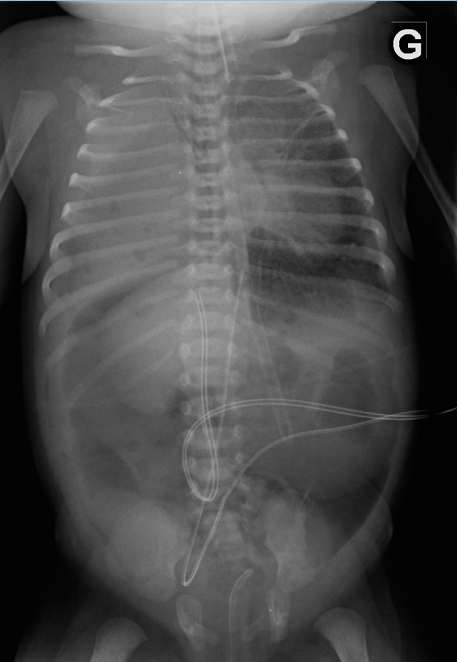

A five-day old girl presented with a pneumopericardium discovered fortuitously on a radiograph (Figure 1). She was born at term with a prenatal diagnosis of right-sided congenital diaphragmatic hernia (CDH) and required high frequency ventilation and inotrope/pressor therapy since birth. On day-6 the pneumopericardium increased and a pneumomediastinum was noted (Figure 2). The newborn remained stable without signs of cardiac tamponade. On day-7, the pneumopericardium/mediastinum resolved and a pneumoperitoneum appeared (Figure 3). The condition of the child improved at the same time and it was possible to gradually diminish ventilation pressures and discontinue inotrope/pressor therapy. No intestinal perforation was noted during surgery a few hours later.

Figure 1: X-ray at day-5. Pneumopericardium.

Figure 3 : X-ray at day-7. Pneumopericardium and pneumomediastinum resolution and apparition of pneumoperitoneum.